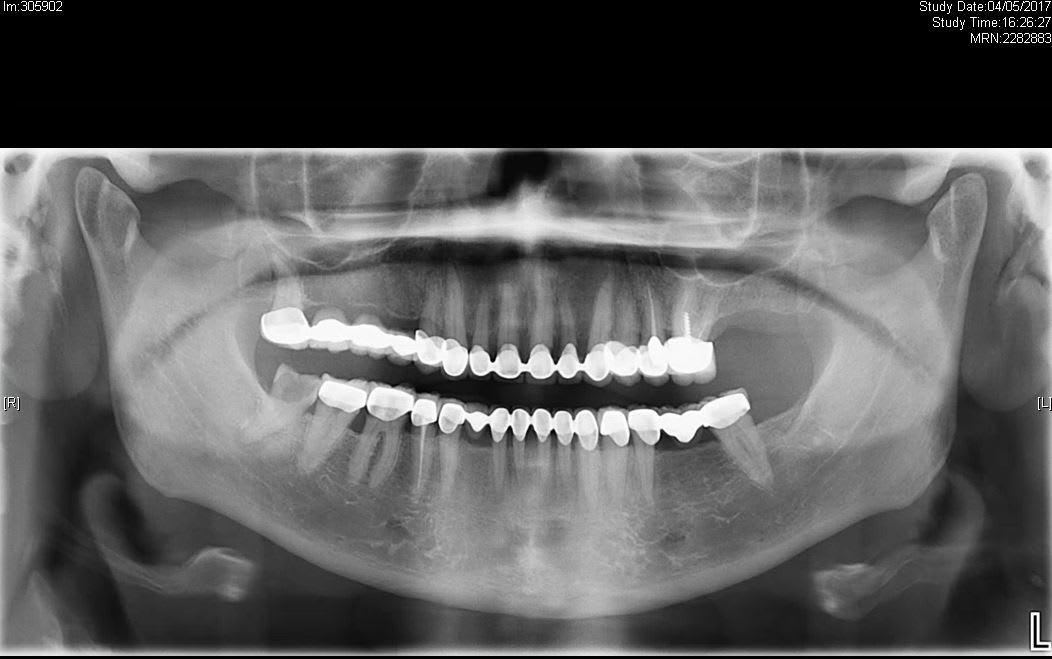

Voici un joli cas que j'ai vu ce matin. Ce qui est sympa c'est que j'ai l'historique en radios depuis 2017.

Au départ plenty of teeth coiffées.

A priori conservables même si j'ai lu en diagonale la pano.

La première radio à été prise dans le cadre de l'avulsion de la 48 au CHU, évidemment aucun des soins non urgents (bridge/couronnes/implants) n'a été fait chez nous.

1er RDV en 2017 pour l'avulsion de la 48, rien à signaler hormis le gros soupçon de surtraitement vu la quantité de prothèses.